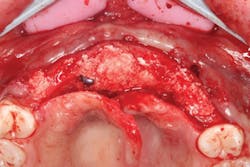

The patient was sedated intravenously in a surgically sterile in-office operatory. The surgical guide was placed over the teeth, checked to make sure it was fully seated without soft tissue impingement or surgical guide excess (figure 5). It was verified that there was no rocking of the guide from either side. An initial pilot drill was made through the guide into the soft tissue. A surgical incision was made with a 15c blade splitting across the keratinized gingiva across the crest of the ridge from Nos. 5–11. A full-thickness flap was elevated buccally and lingually. This released the soft tissue enough to allow the implant drills to go to depth and perform a widening osteotomy. Five osteotomies were made with copious saline irrigation and drill speed of 2,000 rpm. A pilot drill and each sequential step drill guide were used to widen out the osteotomy before placing five 3.5 mm x 10.5 mm MegaGen AnyRidge implants (figure 6). The implants were placed and torqued out at 35 Ncm. (Implants were not placed through the guide, although this was an option. Cover screws were placed. A bone graft with fusion bone binder (figure 7) and platelet-rich fibrin (PRF) were all placed over the implants before suturing with 5.0 polyglycolide sutures (figure 8). The upper partial was relined to take pressure off the soft tissue site.

Figure 7: MFDBA with fusion bone binder covering implants